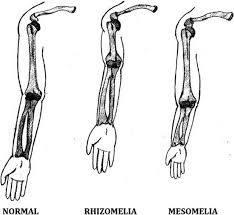

Acromelia

Acromelia

What is Acromelia?

Bone abnormality shortening of distal limb segment.

Acromelia

Mesomelia

What is Mesomelia?

shortening of middle limb segment.

What bones can be Mesomelic ?

tibia

fibula

ulnar

radius

What is Rhizomelic shortening?

Shortening of proximal limb segment

Rhizomelia

Rhizomelia

What bones can be Rhizomelic ?

femur

humerus

What is Micromelia shortening?

Shortening of proximal and distal limb segment

dwarfism